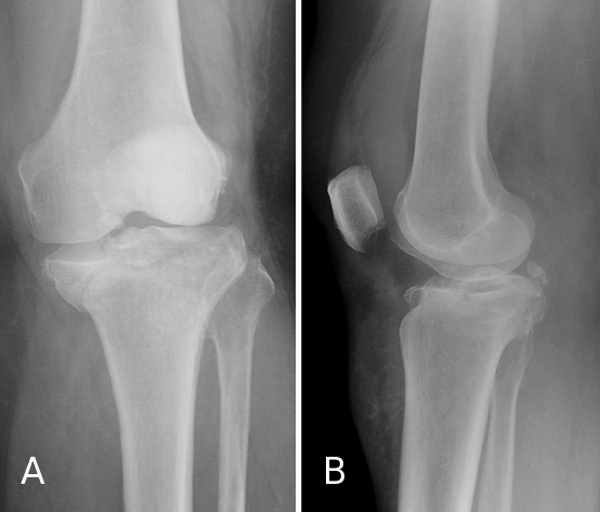

Face (A) et profil (B) d'une patiente victime d'un traumatisme responsable d'une fracture articulaire complexe du tibia proximal. Cette fracture combinant un enfoncement et une séparation des deux plateaux tibiaux entraine des dommages cartilagineux qui exposent, à terme, et même après restauration anatomique de la surface articulaire à une gonarthrose post-traumatique.